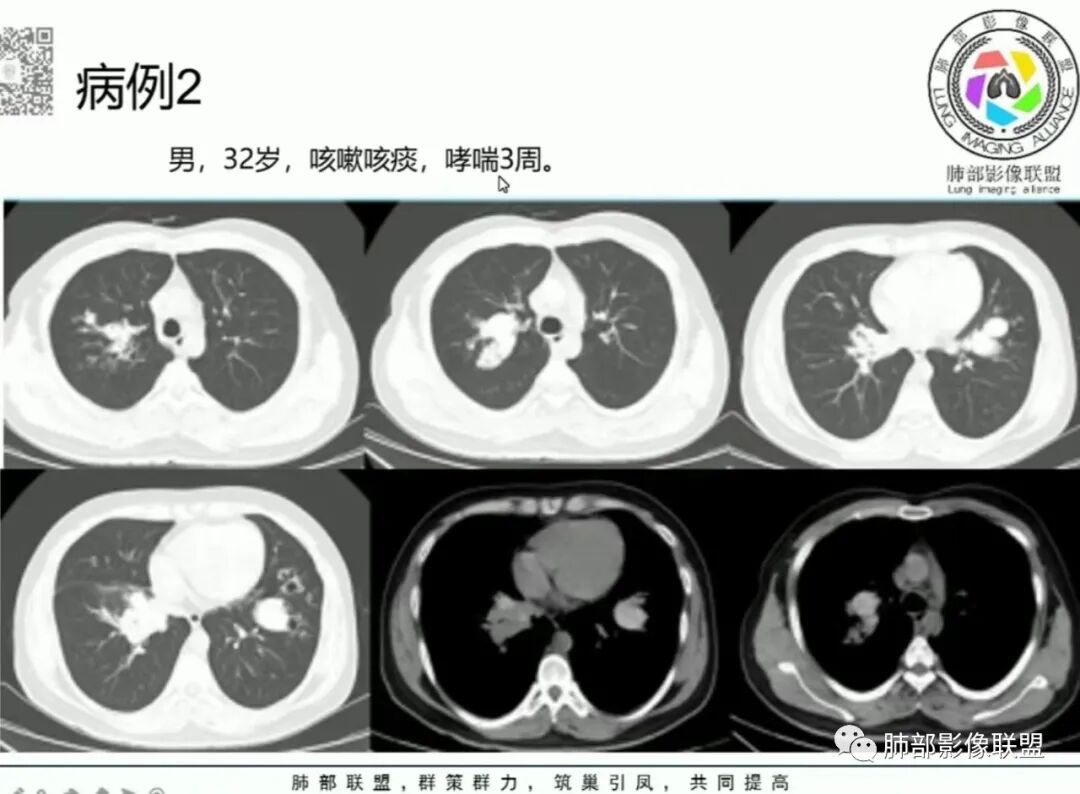

谢加平+中山市三乡镇医院+CT

右肺上叶尖段及中叶内侧段斑块影,边界清,形态不规则,密度不均匀,见钙化斑,右肺上叶尖段病灶呈“芋艿籽”融合,右肺中叶见多发小树芽影,右肺下叶支气管见指套征,纵隔无淋巴结肿大,既往肺TB史,右肺上叶及中叶TB肉芽肿,右肺下叶支气管内膜TB,建议结核T- sport试验和Xpert检查。

双肺多发病变,部分实变,树芽征,支气管管壁增厚、扩张,有结核病史,考虑结核并ABPA

右肺上叶不规则肿块,边缘模糊,周围卫星灶,沿支气管爬行,近端指套样改变,可见高密度影,右肺中叶相近病变,考虑ABPA,鉴别结核

右肺上叶、中叶肿块,性质一致,指套征,高密度不像钙化更像锰铁化,考虑ABPA

右上肺肿块,呈佛手样,内可见斑片状密度增高影,左上肺野可见扩张支气管,(右上肺肿块没给CT值),综和考虑支持ABPA

女,51,咳嗽、咳痰半年。左下叶手术史,术后抗TB治疗史。胸部CT:右肺上叶尖段团片影,边界较清,部分层面周围清楚GGO;形态不规则,近端呈指套样改变;密度不均,内见斑点状高密度灶;胸膜牵拉。右肺中叶内侧段斑片实变影,邻近多发小树芽影?左侧胸廓塌陷,左上叶多发小结节影,支气管扩张样改变,左上叶支气管腔可见钙化影。考虑TB,鉴别ABPA、腺Ca等。

1.中年女性,主因“咳嗽、咳痰半年余”入院,既往史:8年前因左肺病在外院变行左肺叶切除术,诉术后抗结核治疗1年,具体病理等不详。实验室IGE显著增高。

2.胸部CT:右肺上叶及中叶不规则块状影,沿支气管走行方向指套样影,支气阻塞湖嵌塞,腔内可见高密度影。灶周可见磨玻璃,外围见结节影及树芽征。左肺体积缩小,见不规则条索影、胸膜增厚,纵隔牵拉左移。

3.综合分析:结合患者病史及胸部CT主要鉴别ABPA(右肺上叶不规则块影,指套样顺延支气管方向,抗结核治疗1年,肺部病灶仍明显)及继发性肺结核TB(右肺上叶不规则肿块,其可见高密影,边缘模糊,周围卫星灶、树芽征,沿支气管爬行)。

完善气管镜及病理、检验结果(IgE显著增高)等支持ABPA诊断。且给予激素及伊曲康唑治疗后复查胸部CT提示病灶较前吸收,所以诊断明确。